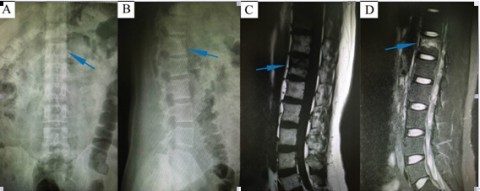

患者马某,男,37岁,甘肃省回族人,因“车祸摔伤致腰背疼痛2天入院”就诊。入院时胸背部疼痛,无法行走,翻身困难。查体显示患者胸腰段有压痛表现,影像学X线检查显示患者胸12椎体可疑骨折,CT及MRI检查后明确胸12骨折,累及椎体前中柱。骨科脊柱组医师集体会诊讨论后,一致认为该患者适合行经皮微创椎弓根置钉内固定术。经过积极、完善的术前准备,于2015年12月11日,在熊敏副主任医师主刀,赵明东副主任医师及丁悦主治医师协助下,成功为该患者实施了该微创手术。 整个手术历时2小时,采用正中旁开4个小切口分别长约2.0cm,术中出血极少(20ml)。术后拍片显示内植物位置理想(图3),患者症状明显缓解。